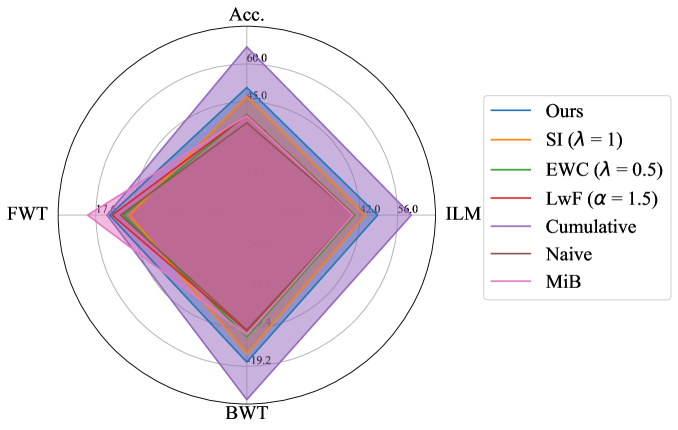

Performance comparison with others: For the considered medical applications, the primary concern will not be on improving zero-shot performance (FWT) but rather on minimizing forgetting (BWT) and enhancing the average DSC of the model (ACC and ILM). While FWT is reported for completeness, our analysis emphasize ACC, ILM, and BWT. Table 2 presents the ACC, ILM, BWT, and FWT values for all methods across sequences S1, S2, S3, and S4. Across all sequences, CL approaches (GDumb, Replay, MiB, LwF, SI, EWC, and the proposed method) mostly outperform naive training, highlighting the importance of mechanisms to mitigate catastrophic forgetting in UNet-based segmentation tasks. Further, as expected, approaches storing past data partially (Replay, GDumb) or fully (cumulative, joint training) show higher performance compared to methods (naive, MiB, LwF, SI, EWC, and the proposed approach) with no access to past exemplars. When comparing the proposed method to other buffer-free approaches (MiB, LwF, SI, EWC), it consistently achieves superior performance in all the sequences S1, S2, S3, and S4. Unlike these existing CL methods, which penalize large deviations from previously learned weights through response-level regularization terms in the training loss, the proposed approach introduces a drift-based dynamic penalization factor along with a latent-level regularization. This drift-based dual distillation allows for more effective mitigation of catastrophic forgetting. The proposed method shows a positive gain in (ACC, ILM, BWT) over best performance achieved among state-of-the art buffer-free approaches (blue colored in Table 2). Specifically, we observe an improvements of (25.51%, 9.23%, 34.34%) in S1, (6.57%, 25.28%, 31.85%) in S2, (4.85%, 11.02%, 40.15%) in S3, and (7.67%, 10.65%, 17.62%) in S4. For intuitive visualization, radar plots for S1, S2, S3, and S4, comparing cumulative, naive, the best-performing buffer-free methods, and the proposed approach are provided in Fig. 6 of Appendix.

Appendix B Radar Plot based Comparison

For intuitive visualization, Fig. 6 provides a radar plot comparing cumulative, naive, the best-performing buffer-free CL methods, and the proposed approach. In all the formulated dataset sequences, the proposed method demonstrates clear superiority over all other approaches except cumulative, which serves as the upper performance bound.